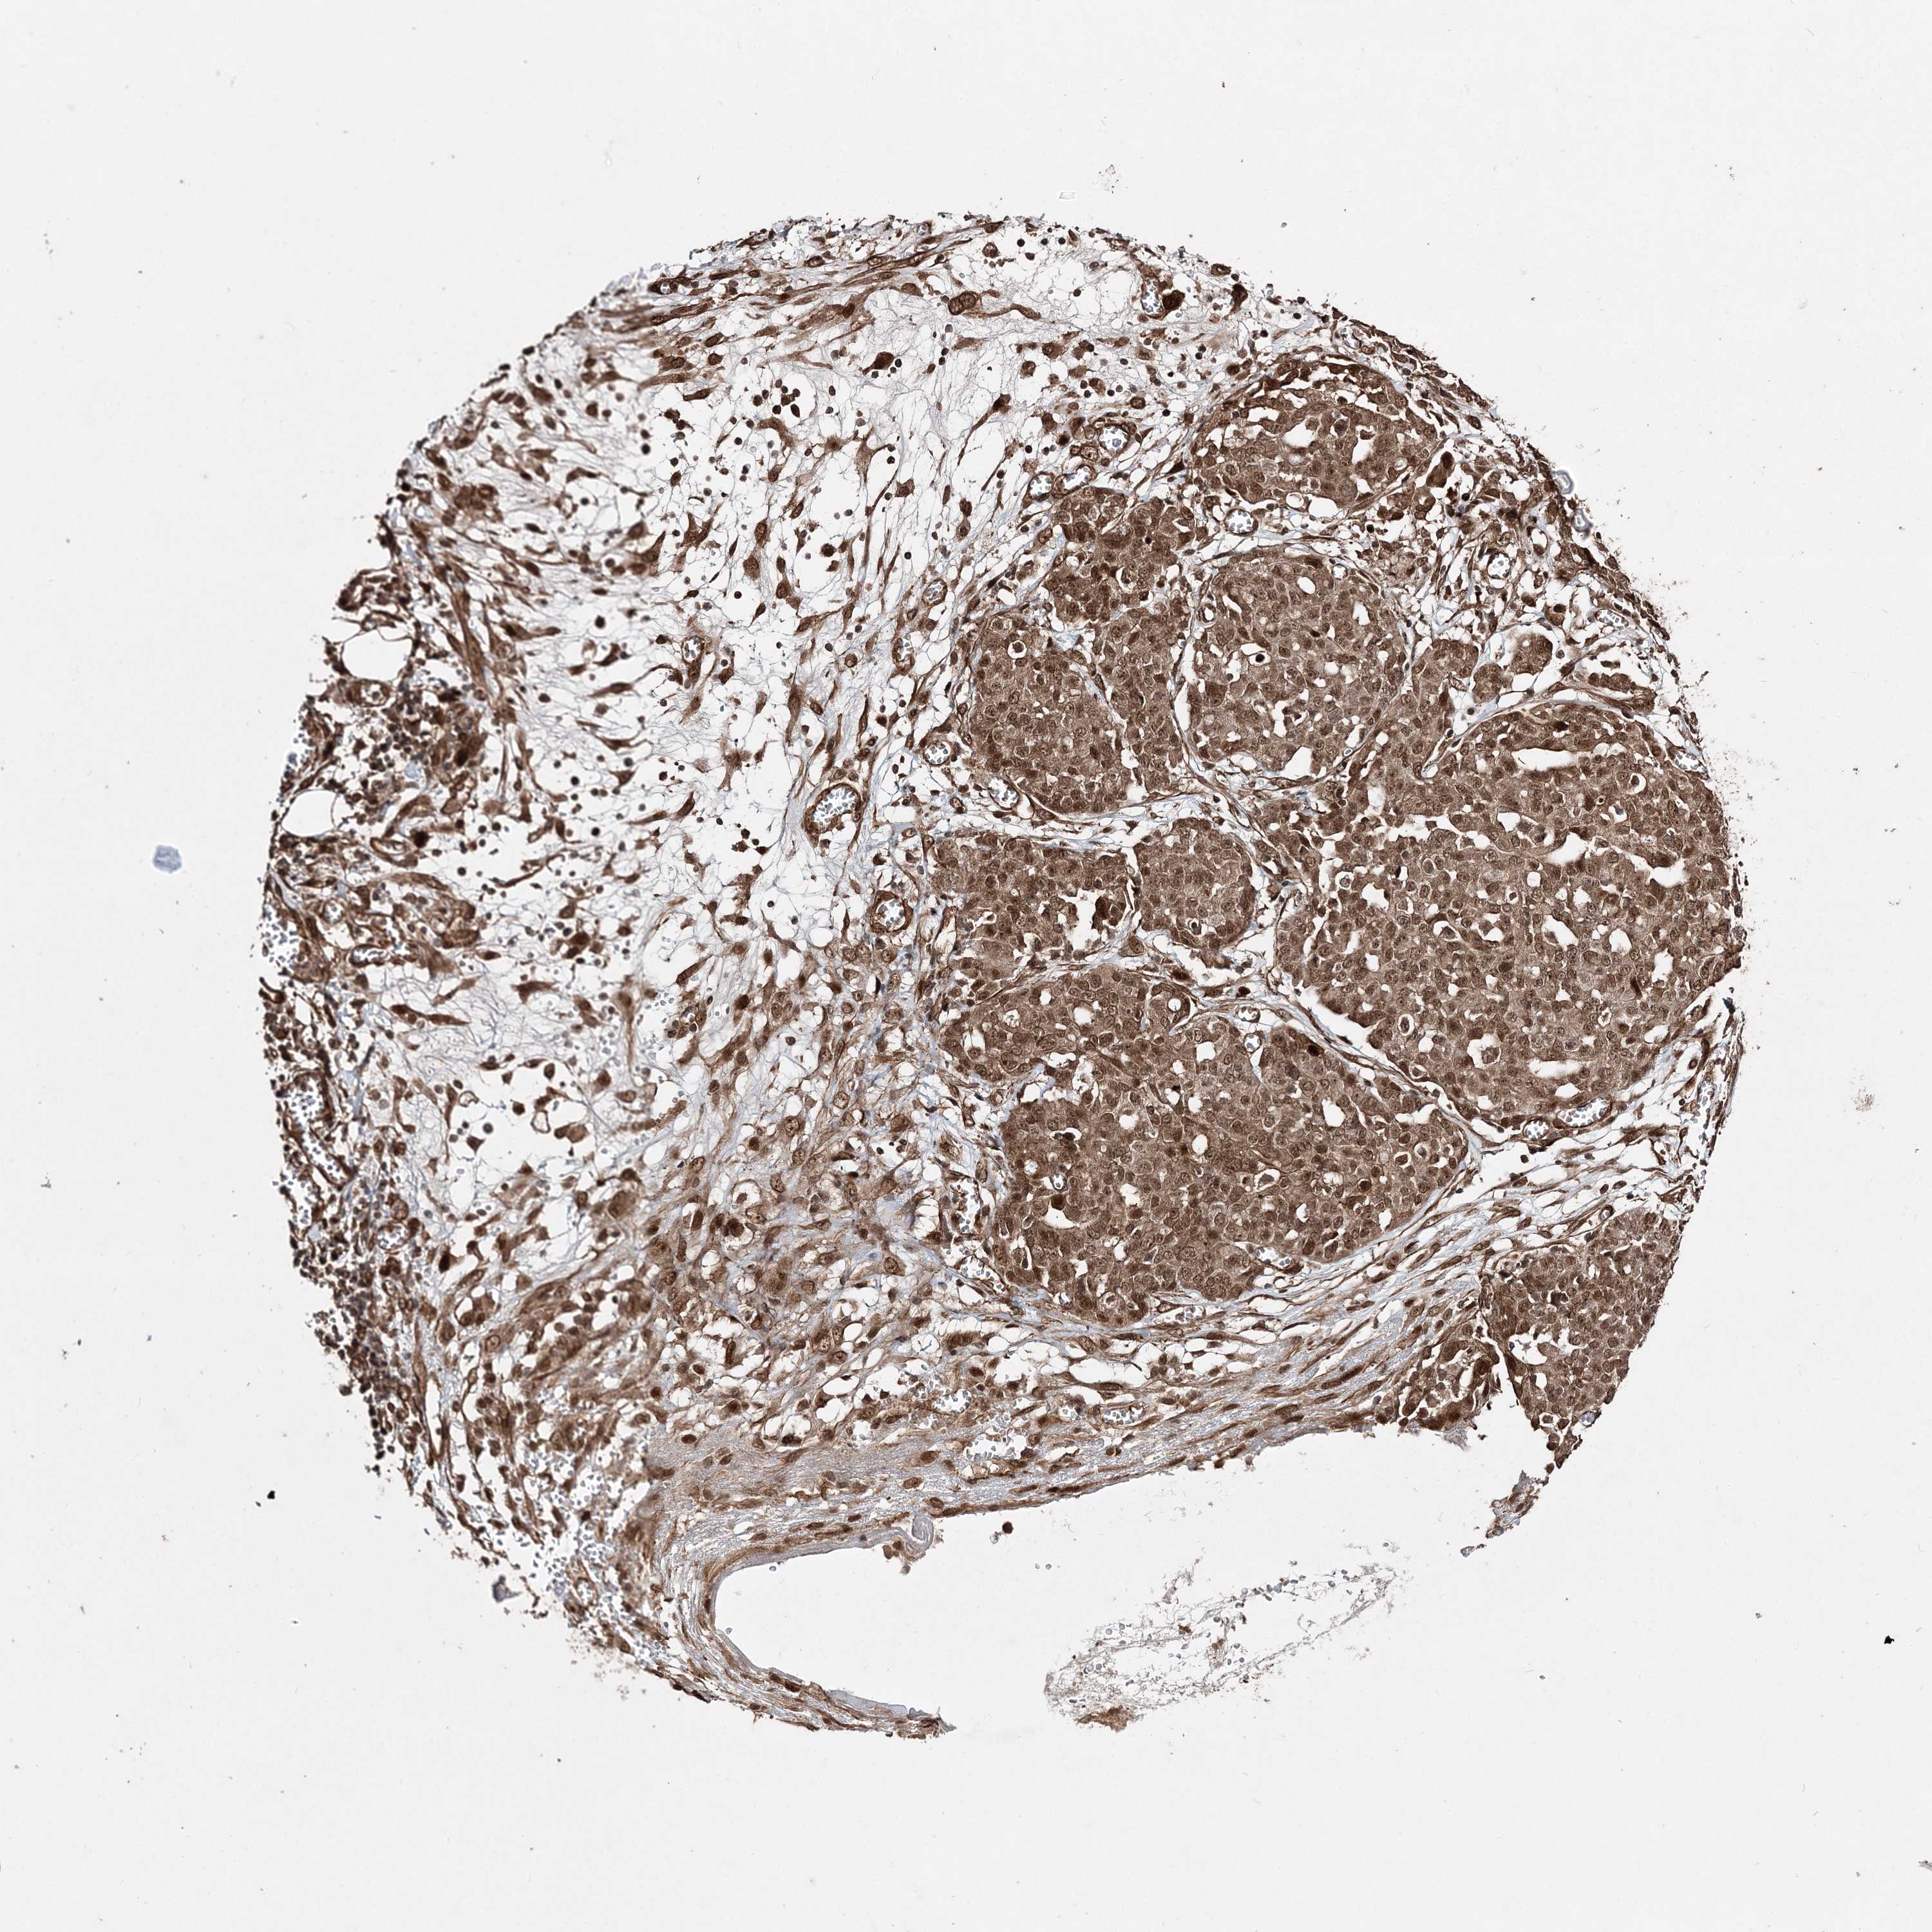

OVARIAN CANCER - Protein expressioni

A mouse-over function shows sample information and annotation data. Click on an image to view it in a full screen mode. Samples can be filtered based on level of antibody staining by selecting one or several of the following categories: high, medium, low and not detected. The assay and annotation is described here.

Note that samples used for immunohistochemistry by the Human Protein Atlas do not correspond to samples in the TCGA dataset.

Antibody stainingi

Antibody staining in the annotated cell types in the current human tissue is reported as not detected, low, medium, or high, based on conventional immunohistochemistry profiling in selected tissues. This score is based on the combination of the staining intensity and fraction of stained cells.

Each image is clickable and will lead to virtual microscopy that enables deeper exploration of all samples and also displays staining intensity scores, fraction scores and subcellular localization as well as patient and tissue information for each sample.

Antibody HPA035048

Antibody HPA035049

Cystadenocarcinoma, serous, NOS

Carcinoma, endometroid

Cystadenocarcinoma, mucinous, NOS

Carcinoma, NOS